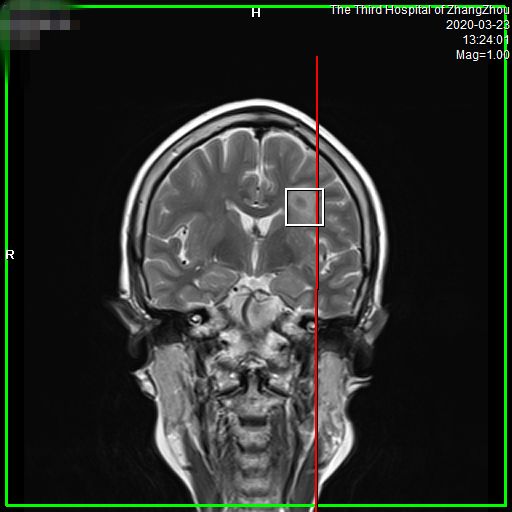

介绍之前,先抛一张我的“帅气照”。

图像更清晰、诊断更精准

• 图像更清晰,病变细节显而易见。对中枢神经系统如头、颈部疾病,以及腹盆部、骨肌系统、乳腺等区域病变检出更敏感,可早发现、早诊断和早治疗。

• 信噪比高,能更早发现小病灶。有关数据显示,对于各类疾病,特别是神经系统和体部系统疾病,可以提前发现病灶,给患者治疗带来了充分的时间,大大提高了病变的诊断水平,让疾病无处可逃,为广大患者带来福音。